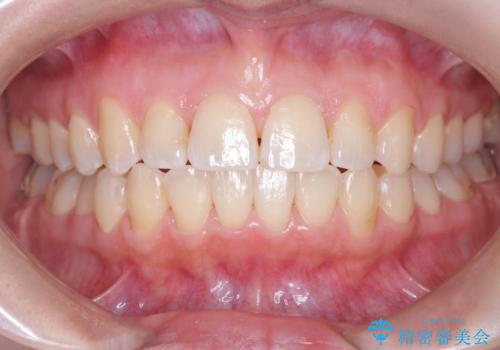

右下第二小臼歯の舌側転移の改善

- 患者様は、右下第二小臼歯が舌側に転移していることが主訴でした。診断の結果、抜歯を伴う矯正治療も検討しましたが、奥歯の遠心移動とIPR(インタープロキシマルリダクション)を行うことで、非抜歯で矯正を進めることが可能であると判断しました。治療計画では、審美ワイヤーを用いた2年間の治療で、歯列を整えつつ、臼歯関係や正中のバランスを維持しながら進めました。

非抜歯矯正では、歯の動きを慎重に調整することが求められます。本症例では、奥歯を遠心に移動させることで、舌側に転移した右下第二小臼歯の位置を改善しました。また、IPRを行うことで歯間スペースを確保し、無理なく歯列の調整を行いました。非抜歯での治療は、特に臼歯関係や正中を保ちながら治療できるというメリットがあり、最終的にはバランスの取れた歯並びを実現できました。審美ワイヤーを使用したことで、治療中も目立ちにくく、患者様の見た目にも配慮した治療を行いました。